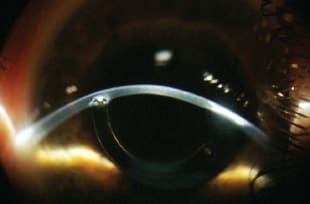

This 23-year-old woman with bilateral keratoconus had intracorneal ring implants in both eyes. She complained of poor vision, contact lens intolerance and many prior GP lens fittings with different specialists. Her best-corrected visual acuity with spectacles was 20/40. She was disappointed that she did not have better quality vision. Figure 4 shows the anterior segment upon evaluation.

Figure 4. Intracorneal ring segments very close to each other at 8 o'clock.

In this case, the corneal ring segments together formed a higher elevation pattern along the tunnel ducts, but they were positioned close to each other so it was possible to achieve a good fitting relationship. We fitted an Ultracone PCR GP lens. We modified the second zone to maintain the lens positioned superi-orly where the best lens-to-cornea fitting relationship was achieved. If we fit a lens with the standard secondary aspheric curve, it tended to drop (Figure 5a). Comfort was achieved, corneal physiological health was maintained, and final visual acuity was 20/20 (Figure 5b).

Figure 5a. Initial test with Ultracone PCR (OD).

Figure 5b. Ultracone PCR custom modified (OD).